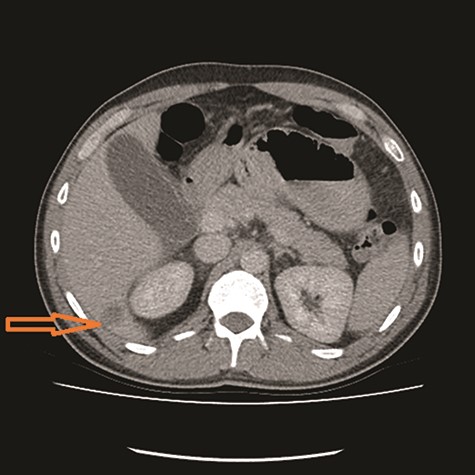

CT showed high-grade proximal jejunal obstruction secondary to a locally infiltrative jejunal mass (Fig. 1) suspicious for carcinoma. There was disseminated peritoneal carcinomatosis with a small volume of ascites and two hepatic metastases (Figs 2–4). A liver biopsy confirmed metastatic deposit of intestinal origin that was positive for CK20 and CDX2 and negative for CK7 and TTF1. There was a mutation in codon 61 of the NRAS gene with no sign of microsatellite instability. Diagnosis of jejunal adenocarcinoma was made.